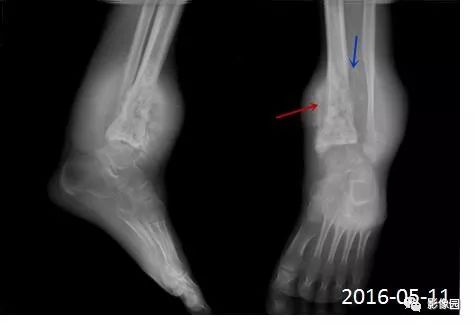

【影像学检查】2016-01-05

2016-05-11复查

评论:前片X线示左胫骨下段及干骺端病变,髓腔内密度不均匀增高,内侧骨皮质可见骨质破坏,可见骨膜反应。CT示病灶内见多发斑片状肿瘤骨(黄色箭头),周围可见针状骨膜反应(红色箭头)。周围软组织肿胀。MRI示胫骨下段以长T1、长2信号为主的混杂信号影,未跨越胫距关节面,周围未见明显软组织肿块。周围软组织广泛片状长T1长T2信号影。复查X线示病变较前片明显进展,左侧胫骨远段及干骺端骨质破坏,周围可见针状骨膜反应及Codman三角(蓝色箭头)形成。相邻左侧腓骨下端、距骨滑车受累。